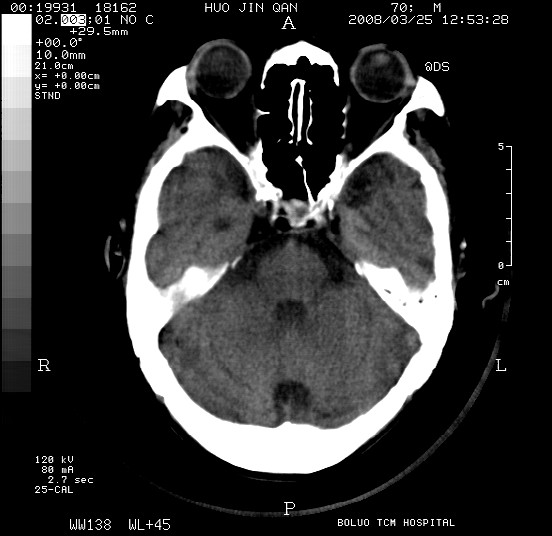

以下是引用随光逐影在2008-3-25 20:15:00的发言:[br]双侧额颞顶部亚急性(或慢性)硬膜下血肿。

以下是引用liuyue在2008-3-26 18:57:00的发言:[br]以下是引用随光逐影在2008-3-25 20:15:00的发言:[br]双侧额颞顶部亚急性(或慢性)硬膜下血肿。 [br]支持![br]可以无明显外伤病史,老年人可以在激烈摇晃或轻微头部碰创头部时,发生硬膜下出血.